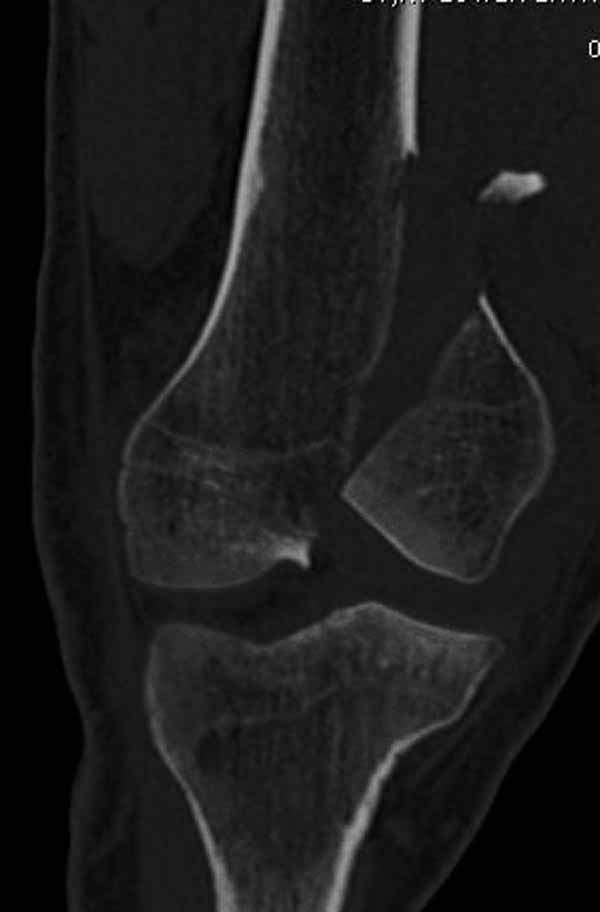

Однако в случае, представленном Константином Никитиным, не может быть применён ни ретроградный ни антеградный остеосинтез. Причина - нереально выполнить вышеуказанные необходимые требования, касающиеся дистальных блокирующих винтов. Из-за низкого перелома латерального мыщелка (перелом Hoffa) невозможно через него провести хотя бы 2 блокирующих винта, поскольку линия перелома мыщелка расположена либо на уровне верхушки межмыщелковой ямки либо незначительно проксимальнее. Поэтому авторам, с моей точки зрения, необходимо прислушаться к рекомендациям Джолдаса.

Рационально ориентироваться на качественный аспект - проблема или решается, или нет. Переломы типа 33C1 или C2 (то есть без фронтального раскалывания мыщелков, как на показанной Вами томограмме) при обычном качестве кости успешно можно фиксировать гвоздями с фронтальными винтами. Получается, их прочностных характеристик уже достаточно.

В приложении пример недавней операции, C3, открытая репозиция, фиксация мыщелков спицами и винтами, ретроградный синтез большеберцовым гвоздем 10,5 мм диаметром, винты 5 мм.